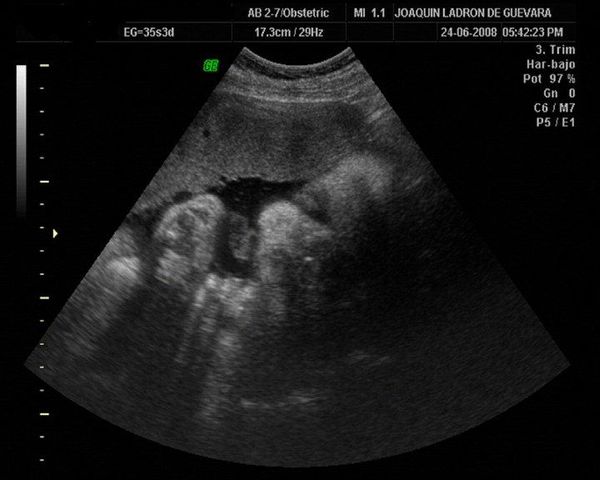

Mi primer bebe

en este año me hicieron mi primera ecografia de mi hijo de 11 años, con la doctora Ines taborda, gran experiencia de vida.